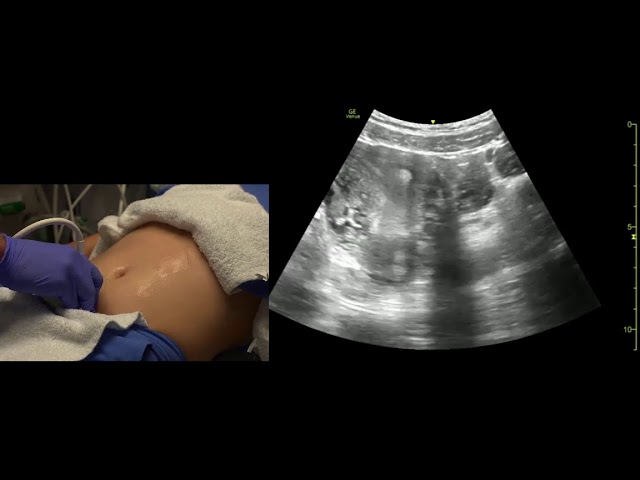

Transabdominal Pelvis Ultrasound Scanning Techniques

In this video, we will review basic techniques of scanning the pelvis in the male and female patient, with attention to the anatomy ...

2:18